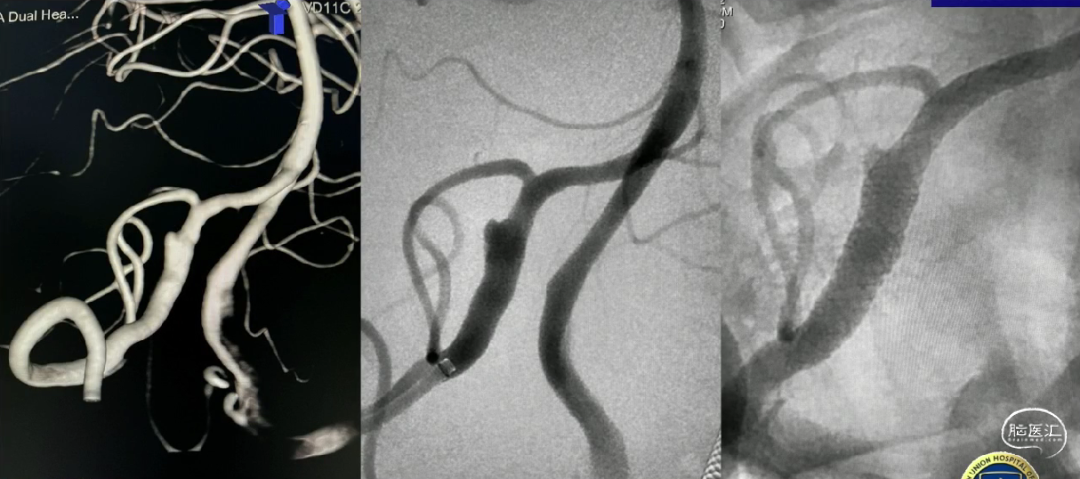

此外:血泡样动脉瘤、基底动脉尤其BVD、胚胎型后交通动脉、分叉处动脉瘤、远端纤细血管动脉瘤

密网时代,即将覆盖所有的前循环侧壁型的动脉瘤;

后循环和分叉部不是血流导向装置的禁地,但需要我们更加审慎的选择病例;